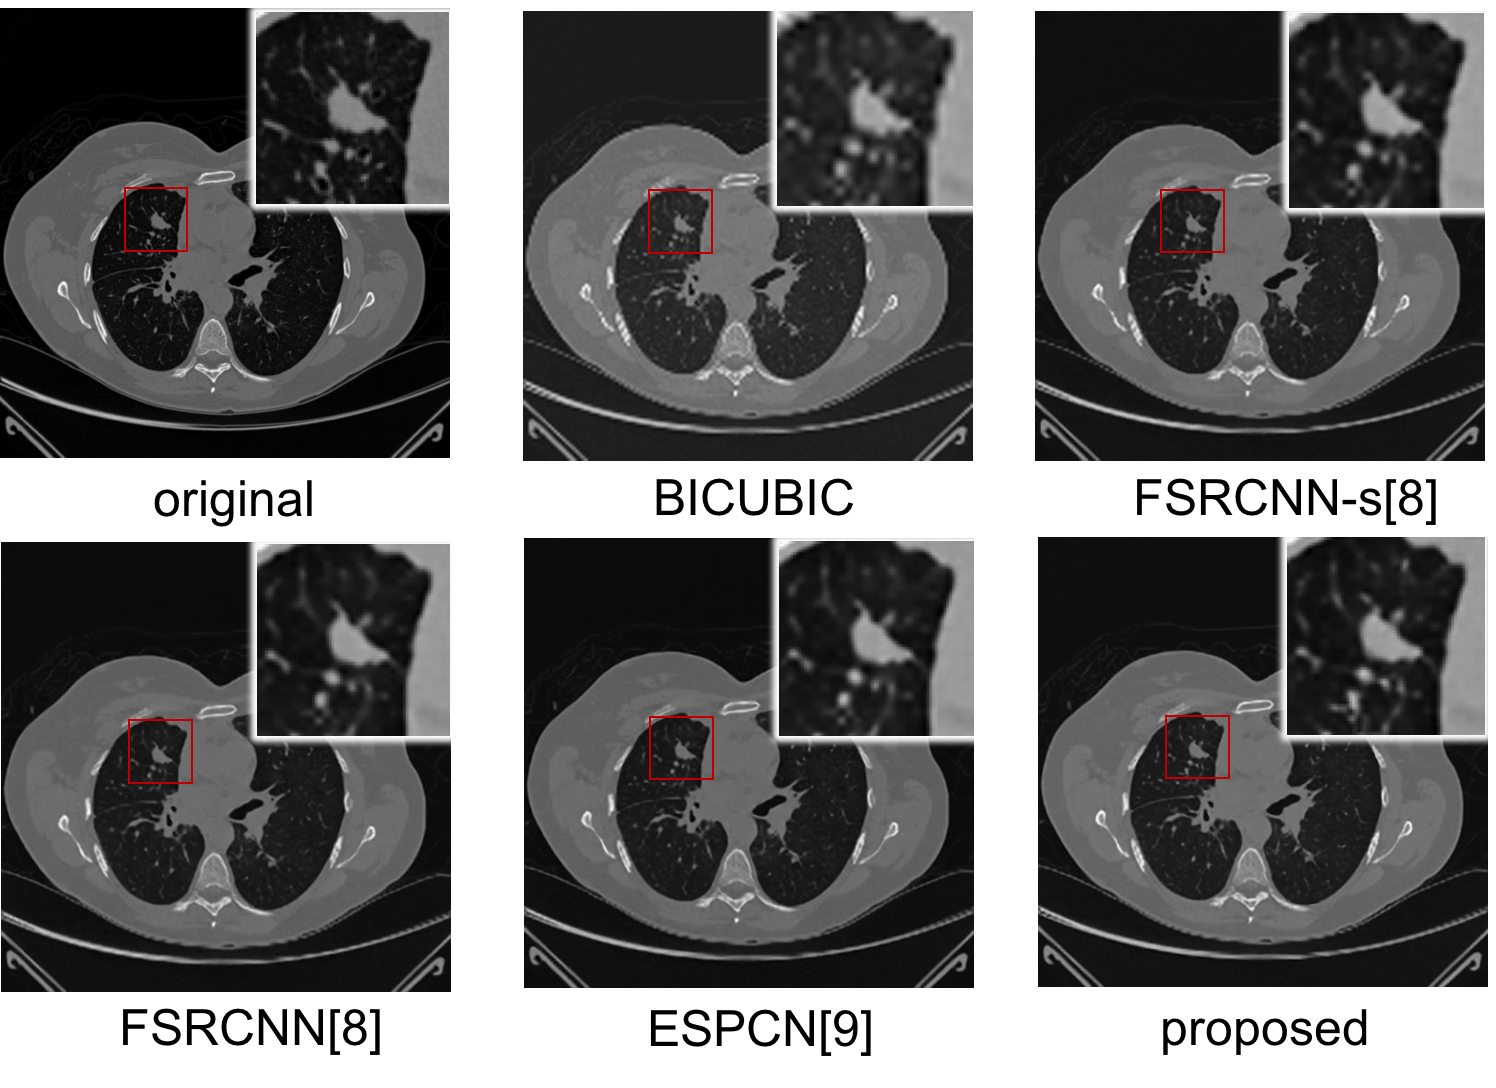

We compare the proposed model to bicubic interpolation and two existing the-state-of-the-art deep learning methods for super resolution image enhancement: 1) FSRCNN [8] and 2) ESPCN [9]. We reimplemented both methods, retraining and testing them in the manner as our proposed method. Both the FSRCNN-s and the FSRCNN architectures used in [8] are compared here. A paired t-test is adopted to determine whether a statistically significant difference exists in mean measurements of PSNR and SSIM when comparing 3DECNN to bicubic, FSRCNN, and ESPCN. Table 1 shows the mean and standard deviation for the four methods in PSNR and SSIM using 5,168 test slices. The paired t-test results show that the proposed method has significantly higher mean PSNR, and mean differences are 2.0183 dB (p-value <2.2e16absent2.2𝑒16<2.2e-16), 0.8357 dB (p-value <2.2e16absent2.2𝑒16<2.2e-16), 0.5406 dB (p-value <2.2e16absent2.2𝑒16<2.2e-16), and 0.4318 dB (p-value <2.2e16absent2.2𝑒16<2.2e-16) for bicubic, FSRCNN-s, FSRCNN and ESPCN, respectively. It also shows that out model has significantly higher SSIM, and the mean differences are 0.03890.03890.0389 (p-value <2.2e16absent2.2𝑒16<2.2e-16), 0.01360.01360.0136 (p-value <2.2e16absent2.2𝑒16<2.2e-16), 0.00980.00980.0098 (p-value <2.2e16absent2.2𝑒16<2.2e-16), and 0.00800.00800.0080 (p-value <2.2e16absent2.2𝑒16<2.2e-16). To subjectively measure the image perceived quality, we also visualize and compare the enhanced images in Fig. 3. The zoomed areas in the figure are lung nodules. As the figures shown, our approach achieved better perceived quality compared to other methods.

Refer to caption

Figure 3: Comparison with the-state-of-the-art works